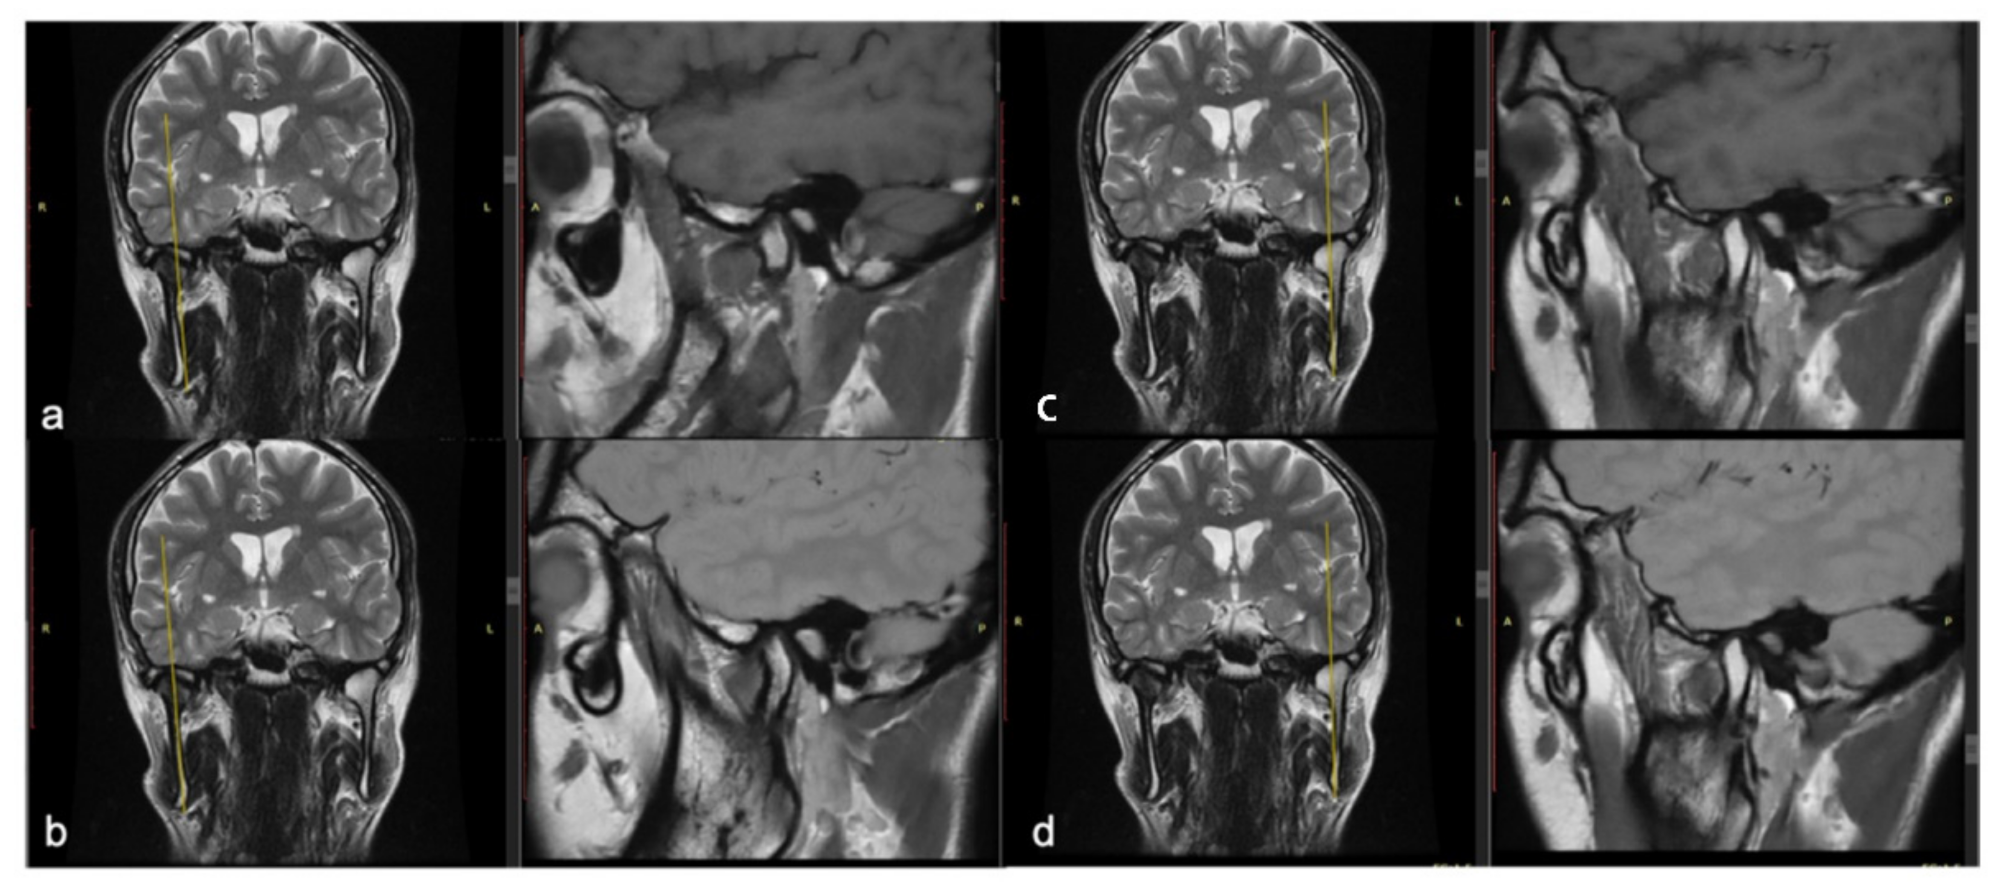

- Minervini, G.; Nucci, L.; Lanza, A.; Femiano, F.; Contaldo, M.; Grassia, V. Temporomandibular disc displacement with reduction treated with anterior repositioning splint: A 2-year clinical and magnetic resonance imaging (MRI) follow-up. J. Biol. Regul. Homeost. Agents 2020, 34, 151–160. [Google Scholar]